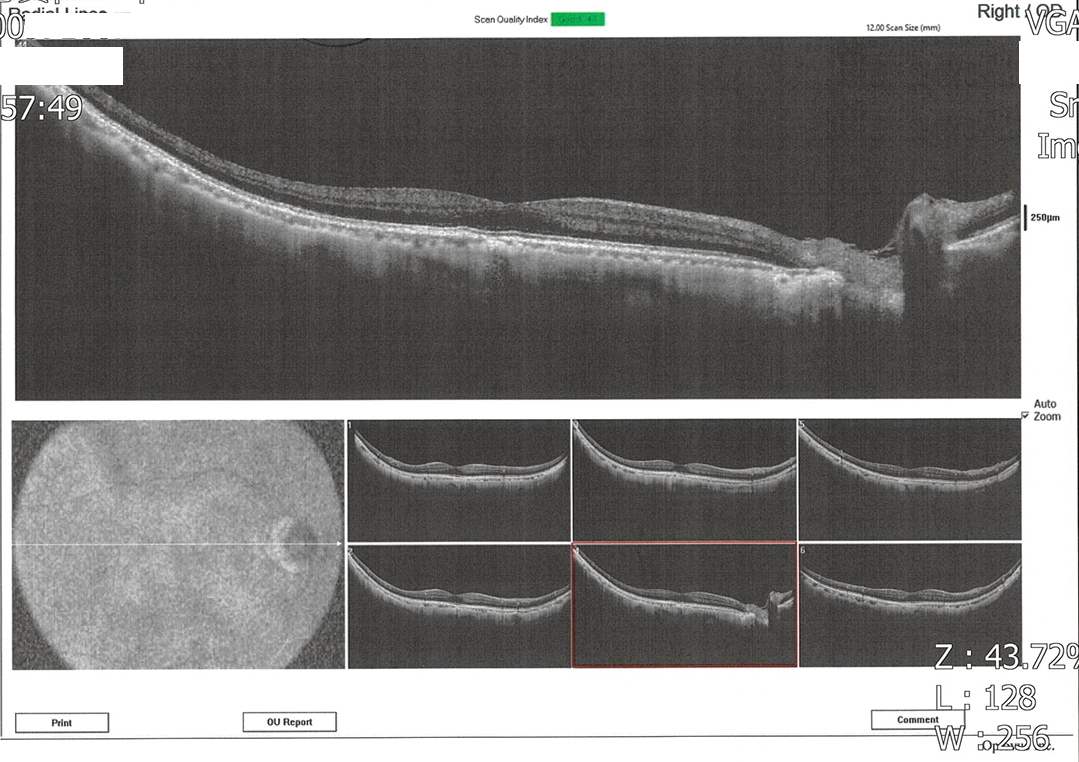

因為左眼在暗處往左看會出現垂直閃光而前往醫院就診,麻煩版主幫忙看一下報告,請問確定是青光眼?嚴重程度?

雙眼杯盤比及視網膜厚度大致正常,但左眼視野敏感度似乎整體性的下降,通常這和白內障比較有關,火勢其他問題,青光眼不會有閃光現象,所以要讓醫師檢查一下眼底,看有沒有視網膜剝離或裂孔,如果你接近50歲左右,也有可能是玻璃體老化液化而拉扯到視網膜,產生閃光